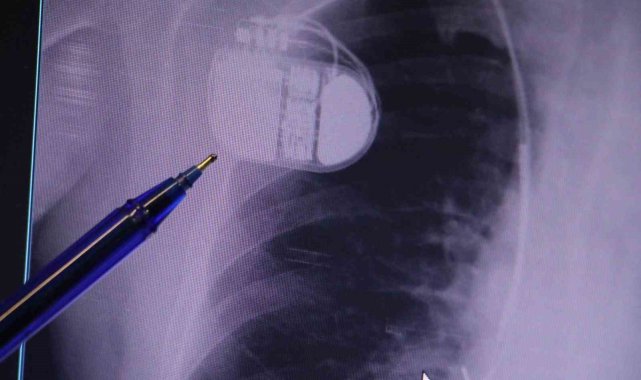

Sivas Medicana Hastanesi Kardiyoloji Uzmanı Dr. İsmail Erdoğu, özellikle kalp pili tedavisinin ani ölümleri önlemede büyük rol oynadığını belirterek, soğuk havalarda kalp pili kullanan hastaların dikkatli olması gerektiği konusunda uyarılarda bulundu.Dünya genelinde kalp hastalıkları, ölüm nedenleri arasında ilk sıralarda yer alıyor. Kalp rahatsızlıkları yalnızca damar tıkanıklığı yaşayan hastalarla sınırlı olmamakla birlikte tansiyon ve şeker hastaları da kalp hastalıkları açısından yüksek risk grubunda bulunuyor. Geçmişte kalp krizi sonrası hastaların yaşam şansı oldukça düşükken, günümüzde erken müdahale ile hayatta kalma oranı büyük ölçüde arttı. Ancak kalp krizinden kurtulan hastalarda zamanla kalp dokularında hasar oluşabiliyor ve bu durum kalp yetersizliği ile ritim bozukluklarına yol açabiliyor.Konuya ilişkin açıklamalarda bulunan Sivas Medicana Hastanesi Kardiyoloji Bölümü Uzmanı Dr. İsmail Erdoğu, kalp pilinin önemine vurgu yaptı. Erdoğu, Yeni nesil kalp pillerinin MR cihazlarına girmeye imkan sağladığı, ancak tarama cihazlarından geçmenin önerilmediğini ifade ederek, "Soğuk hava nedeniyle oluşan titremeler, kalp pilinin kalbin durduğunu sanmasına ve yanlış şoklamaya yol açabilir. Bu nedenle hastalarımızın bu dönemlerde daha dikkatli olmalarını öneriyoruz" dedi."Kalp piline ihtiyaç duyuluyor"Kalp krizleri sonrası kalp dokusunun zarar gördüğünü söyleyen İsmail Erdoğu, "Dünyada artık kalp hastalıkları en sık ölüm sebeplerinden biri. Kalp hastalıklarında çok fazla grup var. Biz kalp hastalıkları deyince sadece kalbinde stent olan ve damarlarında sorun bulunan insanlardan bahsetmiyoruz. Aynı zamanda tansiyon ve şeker hastaları da kalp hastalıklarına aday. Toplumun yaklaşık yüzde 30-35'lik bir kısmını kapsıyoruz. Çok yaygın bir hastalık ve bu hastalıkta teknolojik kapsamda, ilaç konusunda son 30 yılda çok ciddi gelişmeler oldu. Geçmişte insanları hastanelerde kalp krizinden dolayı kaybederken şimdi hastaneye başvurular sonrasında yaşama tutunmak büyük oranda mümkün. Yaşanan ölümler ise genellikle hastaneye gelmeden önce gerçekleşmekte. Kalp krizinden kurtulmanın hastalarda belli bir bedeli oluyor. Kalp krizi sonrası kalpteki dokular zarar görüyor ve kalp yetersizliği oluşuyor. Bu kalp yetersizliği olan kalplerde ritim bozuklukları ve ani ölümler gibi sorunlar gündeme gelebiliyor. Bunlardan uzun vadede korunmak için hastalarda mutlaka bir kalp piline ihtiyaç duyuluyor" dedi."Soğuk havalarda temkinli olunması gerekiyor"Kalp pilleri ile MR cihazına girilebileceğini belirten Erdoğu, "Çok büyük bir ameliyat değil ama yine de ciddi bir cerrahi işlem. Kalp pili, tıpta son 30 yılda yaşanan gelişmelerden en büyüğü. Bir bilgisayarın küçültülüp insan vücuduna konulmuş hali aslında. İnsan ömrünü ciddi oranda uzatan bir tedavi. İnsanlar bir şokla hayata tutunurken, pil olmasaydı öleceğini düşündüğümüz birçok hastamız var. Kalp pilinin bu özelliği, uygun hastalarda ciddi oranda ani ölümü engelliyor. Hastanın başına gelecek bir kalp durması durumunda yanında bir sağlıkçı yoksa, onun ritmini düzeltecek defibrilatör cihazı yoksa hastayı hayatta tutmak mümkün değil. Uygun endikasyonlarda kalp pili olduğu zaman, pil hastaların ritmini algılıyor ve acilde yapılan şoklamayı yaparak hastayı hayata döndürüyor. Kalp pillerinde yeni teknolojilerle MR'a girmek mümkün, tomografiye zaten girebiliyorlar. Tarama cihazlarından geçmelerini uygun görmüyoruz. Bu tarz durumlarda hastalarımız 'kalp pilim var' dediğinde muaf tutuluyorlar. Kalp pilleri ciddi teknolojik cihazlardır. Vücudun içindeki titreşimi, örneğin mikser kullanmak, kolunu sallayacak herhangi bir eylem kalp pilinde olumsuz etki oluşturabilir. Soğuk havalarda vücutta oluşan ciddi titremeler kalp pilinin hafızasını karıştırıp kalbin durduğunu düşündürebilir ve gereksiz şoklama yapabilir. Bu tarz kişilerin soğuk havalarda daha temkinli olması gerekir" diye konuştu.